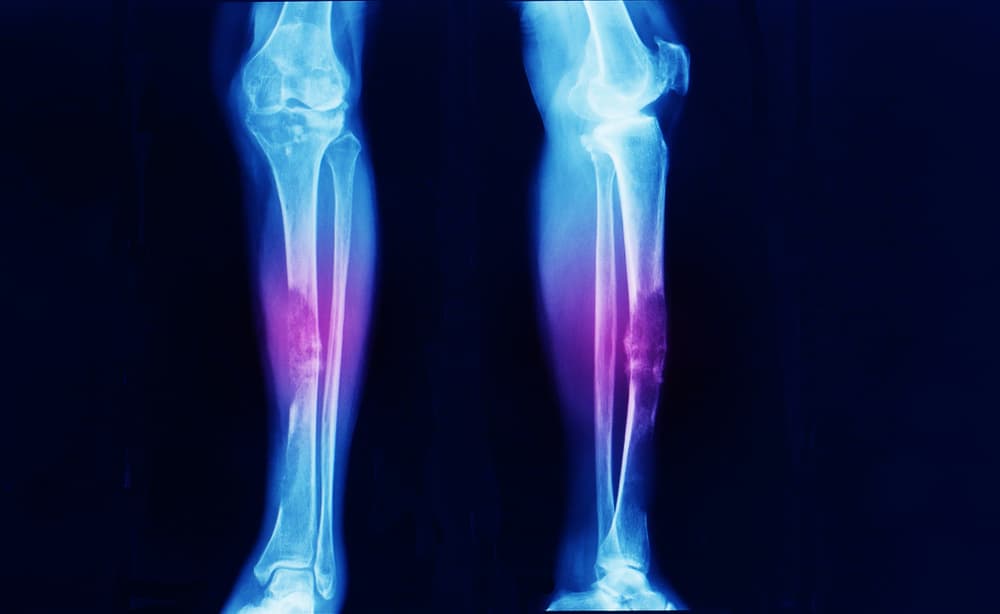

Ang iyong doktor ay maaaring magsagawa ng mga test upang matukoy kung ang cancer ay kumakalat na sa iyong mga buto. Maaari kang magkaroon ng blood testing  upang matukoy ang iyong calcium levels. Ang X-ray, body scan, at/o MRI ay makatutulong sa iyong medical team na makita at mas maunawaan ang kondisyon ng iyong cancer.